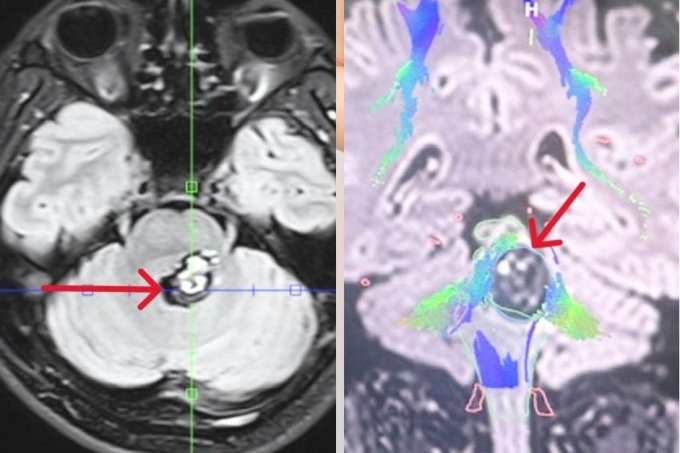

Khối u não của anh Bạch trên hình chụp MRI 3 Tesla (hình trái),bao quanh có nhiều bó sợi thần kinh (màu xanh,hình phải) trên hình chụp DTI. Ảnh: Bệnh viện Đa khoa Tâm Anh

Khối u đã được phát hiện từ 6 năm trước,bác sĩ đánh giá khó mổ,anh Bạch điều trị bằng xạ phẫu Gamma Knife. Gần một năm nay triệu chứng ngày càng nặng hơn,anh uống thuốc giảm đau không bớt. Kết quả chụp MRI 3 Tesla sọ não kết hợp chụp bó sợi thần kinh (DTI) tại Bệnh viện Tâm Anh ghi nhận khối u kích thước 1,5 cm,nằm trong thân não.

Khối u mạch máu ở thân não của anh Bạch có nguy cơ chảy máu dẫn tới đột quỵ xuất huyết não. U càng để lâu sẽ tăng kích thước,mức độ chèn ép các bó sợi thần kinh và cấu trúc não lành xung quanh càng tăng,nguy cơ tử vong đột ngột. U mạch máu của anh Bạch có cấu trúc không đồng đều,khi mổ nguy cơ cao chảy máu khó cầm hoặc phạm phải các bó sợi thần kinh bên cạnh gây suy hô hấp,ngừng tim đột ngột.